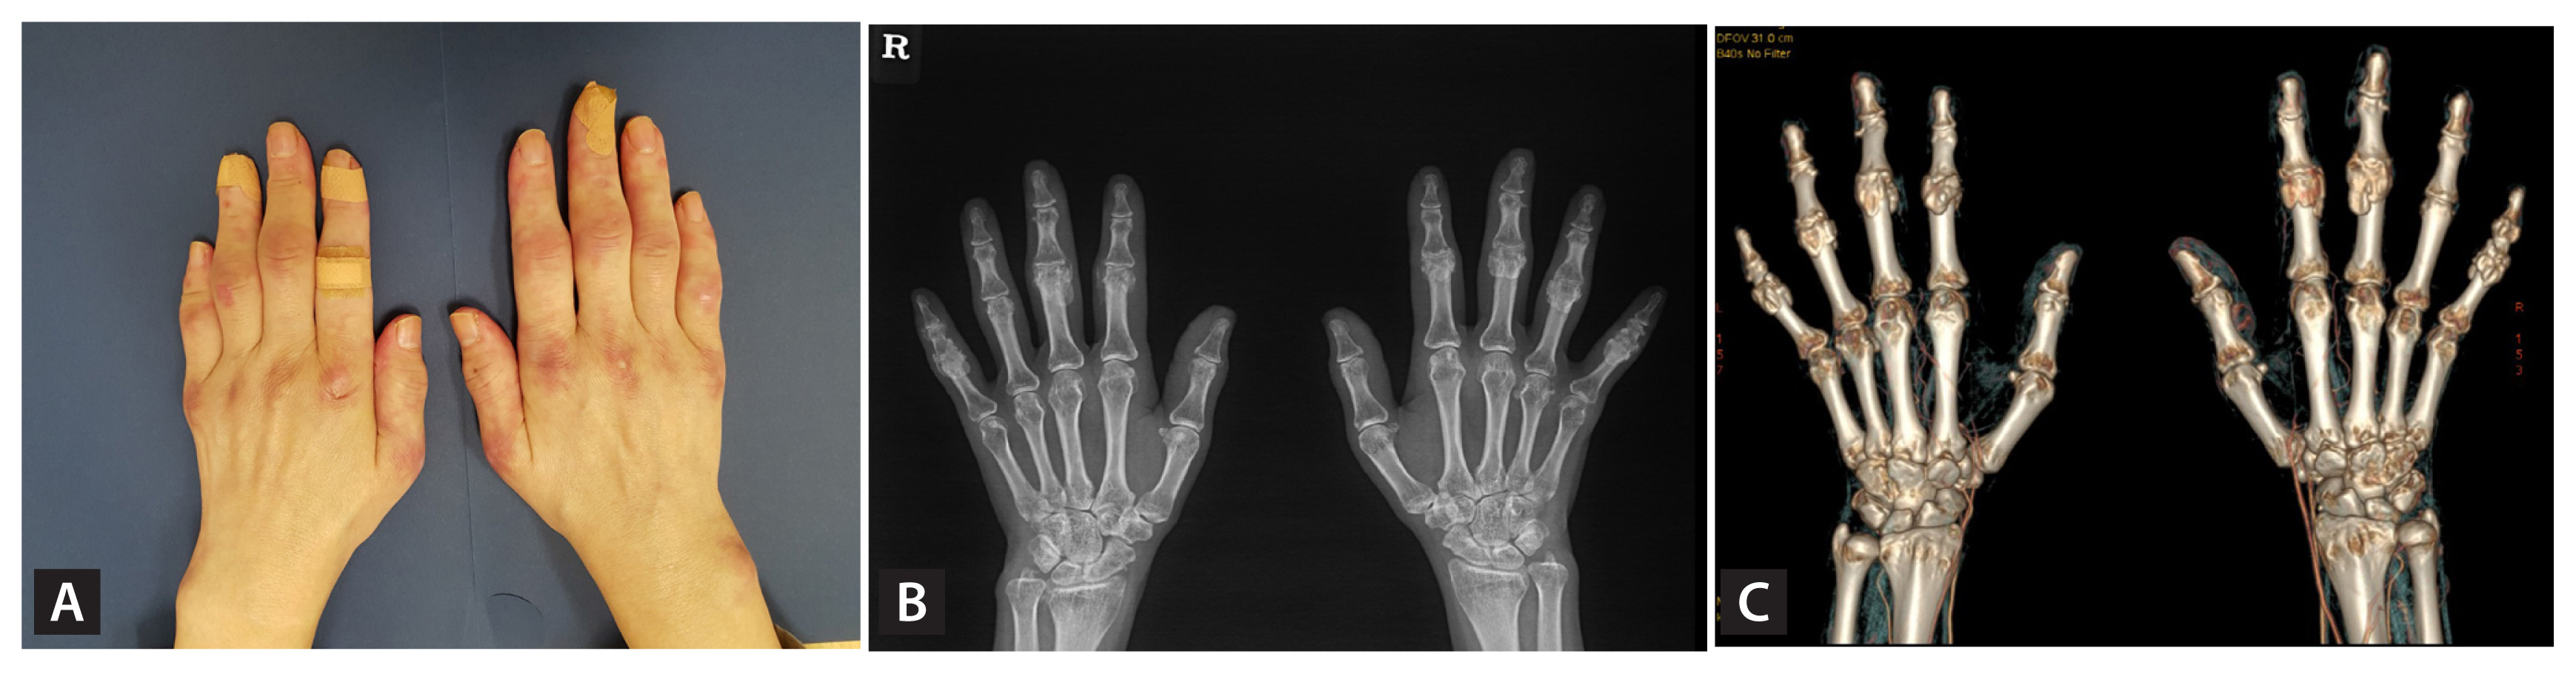

A 49-year old woman presented to rheumatologic clinic with a 3-month history of joint pain. Physical examination revealed erythematous flat lesions over the dorsal surface of metacarpals and interphalangeal regions. Swelling and tenderness were observed in the metacarpophalangeal and proximal interphalangeal (PIP) joints. There was no muscle weakness. Calcinosis cutis was absent. Serologic testing showed elevated rheumatoid factor of 31 IU/mL (reference value, < 15). Anti-cyclic citrullinated peptide antibody was negative. Anti-nuclear antibody was negative, but anti-Ro 52 was positive. Creatinine kinase levels were 54 U/L (reference value, < 270). There was no abnormality on the hand X-ray. A computed tomography scan of the chest showed ground-glass opacities and reported as interstitial lung disease (ILD). A diagnosis of amyopathic dermatomyositis was made according to the Gottron’s papule, arthritis, and ILD. She was treated with prednisolone, hydroxychloroquine, and methotrexate. After treatment, joint pain was diminished, but hand stiffness and skin lesions were persisted. Bony joints in both hands showed progressive enlargement (Fig. 1A), and 2 years later, follow-up hand X-ray showed newly appeared multiple periarticular calcifications in the right 2nd, 3rd, 5th PIP joint and left 2nd to 5th PIP joint and right ulnocarpal joint/radiocarpal joint (Fig. 1B). Dual-energy computed tomography scan revealed periarticular calcifications in the PIP and wrist joints without monosodium urate crystal deposition (Fig. 1C). Thyroid hormones, parathyroid hormone, and vitamin D levels were within normal ranges.

Calcinosis cutis, calcium deposition in cutaneous and subcutaneous tissue, is rare complication of dermatomyositis. The interest of present case is calcinosis was localized only in periarticular space of hands. When patients with rheumatologic disease complained hand stiffness, synovitis is usually considered. It is a rare case of periarticular calcifications of both PIP joints in patients with dermatomyositis who complained of bilateral hand stiffness.